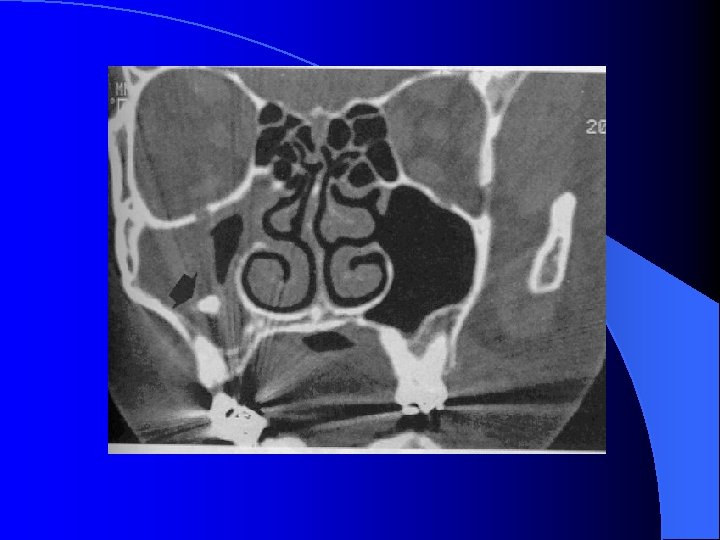

MALADIES INFECTIEUSES RHINO SINUSIENNES SINUSITE MAXILLAIRE CHRONIQUE FORMES CLINIQUES SMC Aspergillaire: • ATCD de soins dentaires maxillaires • RX, TDM: Micro-opacité de tonalité métallique au sein d’une opacité complète du sinus maxillaire • Prise en charge chirurgicale : Méatotomie moyenne endonasale pour détersion du sinus maxillaire et exérèse de la truffe aspergillaire Voie vestibulaire type Caldwell-Luc • Aucune indication à un traitement médical antimycosique SMC de l’enfant: (rare) Contexte de pathologie générale à recher Mucoviscidose, Dysfonction ciliaire (Kartagener)

MALADIES INFECTIEUSES RHINO SINUSIENNES SINUSITE MAXILLAIRE CHRONIQUE IMAGERIE